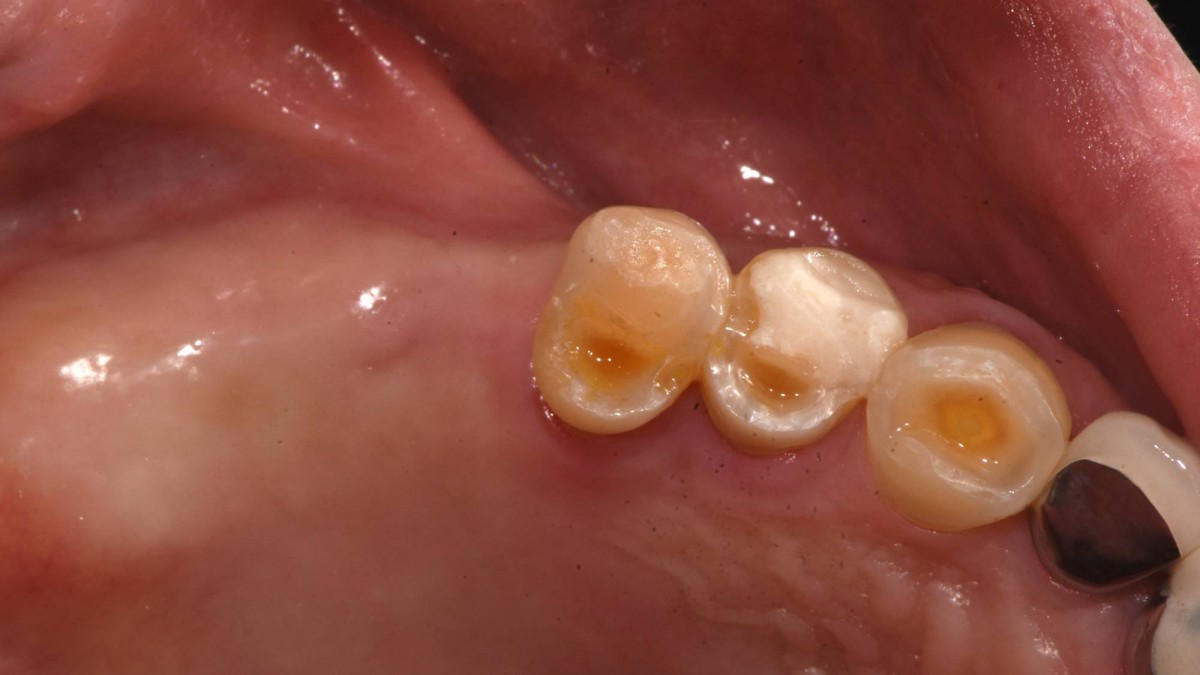

Socket Lift and Implant Placement in the right maxilla.

<GCacg> A 56-year-old male patient complained of pain in the right upper and lower jaws. And he wanted the upper first molar to be pulled out first.